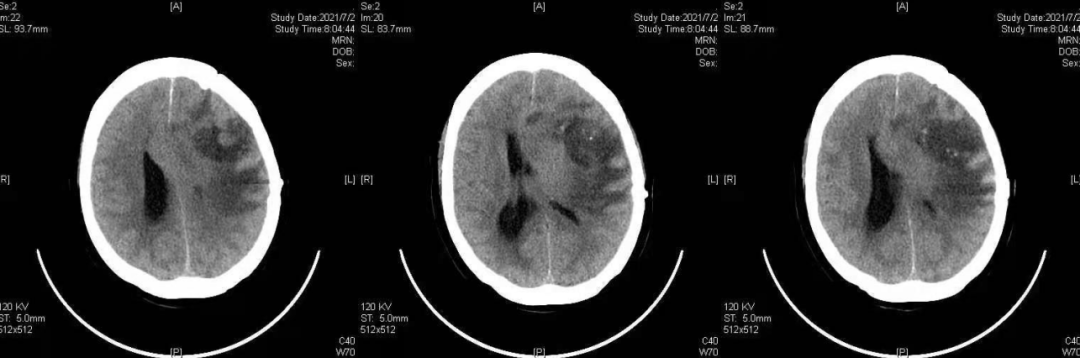

胶质瘤CT

去当地医院就诊,行头颅ct检查示:右侧额叶恶性肿瘤,转移瘤或胶质瘤